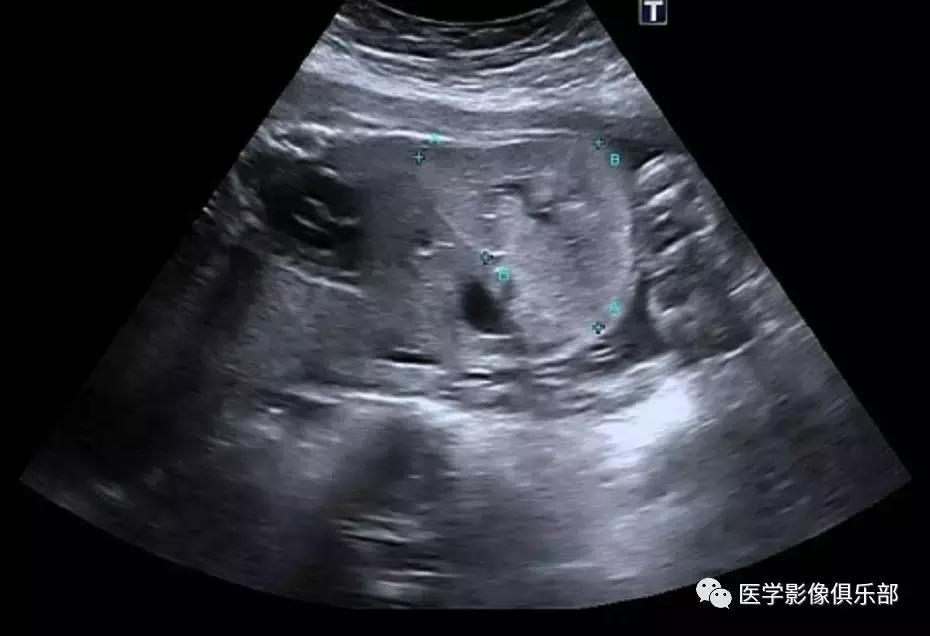

[病例举例]:常规产科超声显示胎龄26周胎儿畸形。

胎儿超声显示双肾明显增大,回声增强,羊水量较少。